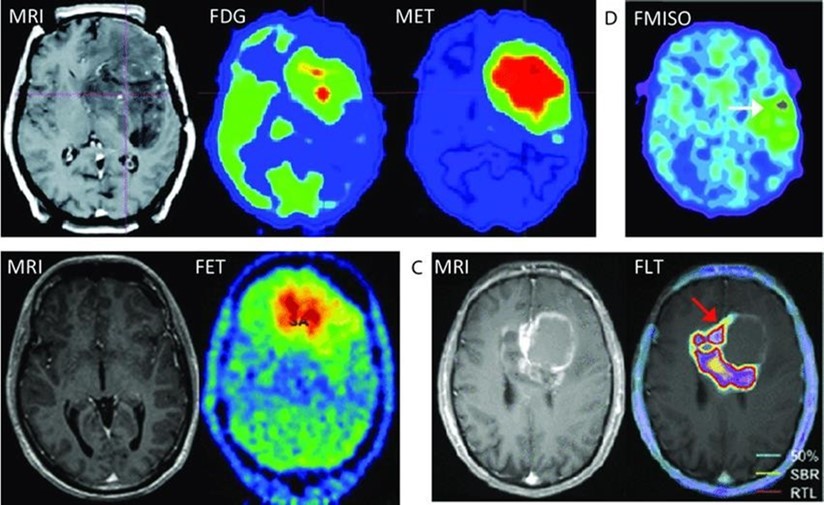

It is a non–invasive method. It can be used to monitor the chemical changes of tissues. We can simultaneously evaluate several metabolites. Two examples of where MRS is very helpful in the brain: The invasion of the tumor (Glioblastoma multiform (GBM) into the surrounding tissues, which is not clear in normal T2 images, but can be determined by MRS. By MRS, it is possible to distinguish two types of lesions that look similar to each other in normal MRI images (such as tumor recurrence and tumor necrosis after radiotherapy). MRS imaging has found wide applications in the field of cancer diagnosis. Among the fields of clinical application of MRS, we can mention the diagnosis (between normal and cancerous tissue, different types of cancer and neoplastic from non–neoplastic), designing the best treatment regimens for each patient, and monitoring the patient after treatment. MRS in tumors: In brain tumors, spectroscopy can determine the degree of malignancy. As malignancy increases, NAA and creatine decrease and choline, lactate and fat increase. Fat is seen in the necrotic parts of the tumor. Lactate concentration increases in rapidly growing tumors due to anaerobic glycolysis. Diagnosing tumor recurrence from the effects of radiotherapy: Increased choline is a marker for tumor recurrence. Changes due to radiotherapy usually decrease NAA, creatine and choline. If necrosis has occurred as a result of radiotherapy, fat and lactate can also be seen in the spectrum. Molecular imaging using spectroscopy Cerebral ischemia and infarction: When the brain suffers from ischemia, anaerobic respiration of glucose is used and lactate increases. Choline increases and NAA and creatine decrease. If it happens after ischemia, the fat signal is also seen. trauma: It is a useful method to assess the degree of nerve damage and predict the results. The clinical consequences are opposite to the NAA/Cr ratio, and the observation of lactate and fat indicates the seriousness of the condition. infectious diseases: decrease naa Inside the abscess, lactate, alanine, cytosolic acid and acetate increase. Alzheimer: In the advanced stages of Alzheimer's, NAA decreases and myo–inositol increases. MS: The increase of choline and lactate has shown that the increase of choline can be due to the increase of phospholipid as a result of breaking the myelin of the cell and the increase of lactate is due to the increase of the anaerobic respiration of the cell due to the increase of the cell metabolism. In addition, there is evidence of increased lipids, and most importantly, decreased NAA, which is caused by nerve damage. And recently, it has been found that glutamate and myoinositol levels increase in acute MS lesions. Parkinson: In most studies in Parkinson's disease, no changes in metabolites have been observed, only when Parkinson's has caused brain atrophy, a decrease in NAA in the basal ganglia has been observed (Figure 3, Figure 4, Figure 5, Figure 6).

Figure 3.Different spectra metabolites in different areas of the human body.